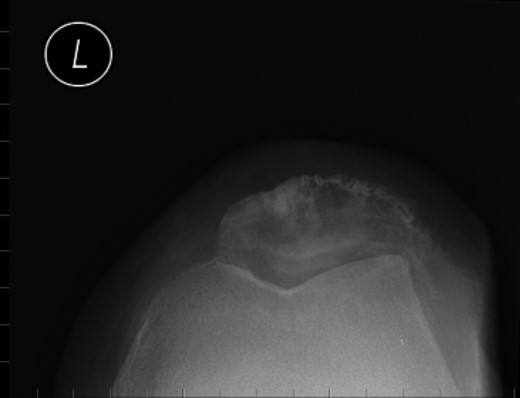

Nineteen months earlier the patient had consulted his general practitioner complaining of left knee pain. Radiographs performed at that time were reported to show joint space narrowing within the patello-femoral compartment as well as early joint space narrowing within the medial compartment. A subchondral lucency was also noted within the patella which was described as a subarticular cyst secondary to the previously mentioned patello-femoral degeneration (Figs 1–3).

The absence of associated features of systemic disease, as well as radiographic appearances in keeping with early patello-femoral osteoarthritis (OA), account for the delay in diagnosis. The initial images suggest mild degeneration but, whilst subarticular cysts are a radiographic feature of OA, the lesion shown in this case is larger than would be expected with the level of disease shown elsewhere in the joint.